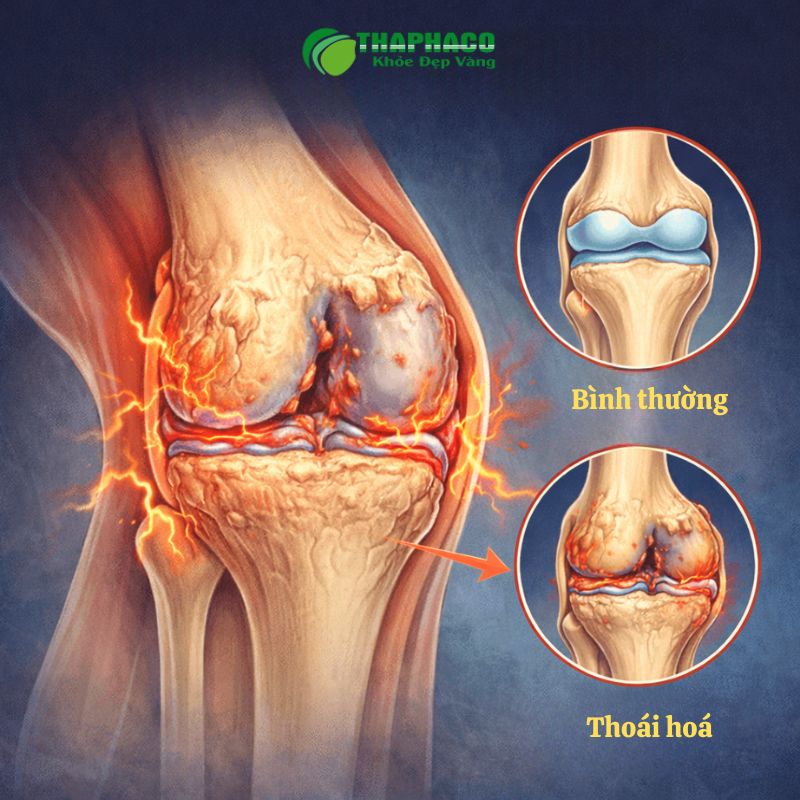

Thoái hóa khớp gối là tình trạng sụn khớp bị tổn thương, bào mòn và mất đi tính đàn hồi theo thời gian, dẫn đến đau nhức, cứng khớp và hạn chế vận động. Đây là bệnh mạn tính tiến triển từ từ, ảnh hưởng lớn đến chất lượng cuộc sống.

Thoái hóa khớp gối, hay còn gọi là viêm xương khớp gối (Osteoarthritis of the Knee), là một bệnh lý mạn tính đặc trưng bởi sự tổn thương và bào mòn sụn khớp bao bọc đầu xương đùi và xương chày tại khớp gối. Sụn khớp đóng vai trò như một lớp đệm êm ái, giúp giảm ma sát và hấp thụ lực khi chúng ta vận động. Khi sụn bị thoái hóa, bề mặt trở nên thô ráp, nứt nẻ, thậm chí là biến mất hoàn toàn, khiến các xương cọ xát trực tiếp vào nhau.

Không chỉ sụn khớp, quá trình thoái hóa còn ảnh hưởng đến các cấu trúc khác trong khớp gối:

- Xương dưới sụn: Khi sụn bị mòn, xương dưới sụn phải chịu áp lực lớn hơn, dẫn đến phản ứng tạo xương mới (gai xương) và xơ hóa xương.

- Màng hoạt dịch: Có thể bị viêm, gây sưng và tiết dịch bất thường, dẫn đến tràn dịch khớp.

- Dây chằng và gân: Yếu đi hoặc bị tổn thương, làm giảm tính ổn định của khớp.

Thoái hóa khớp gối khác với các bệnh viêm khớp khác như viêm khớp dạng thấp ở chỗ, đây là một quá trình thoái hóa cơ học chủ yếu do lão hóa, quá tải hoặc chấn thương, chứ không phải do phản ứng tự miễn của cơ thể. Bệnh thường tiến triển chậm, từ từ và nặng dần theo thời gian nếu không được can thiệp kịp thời.